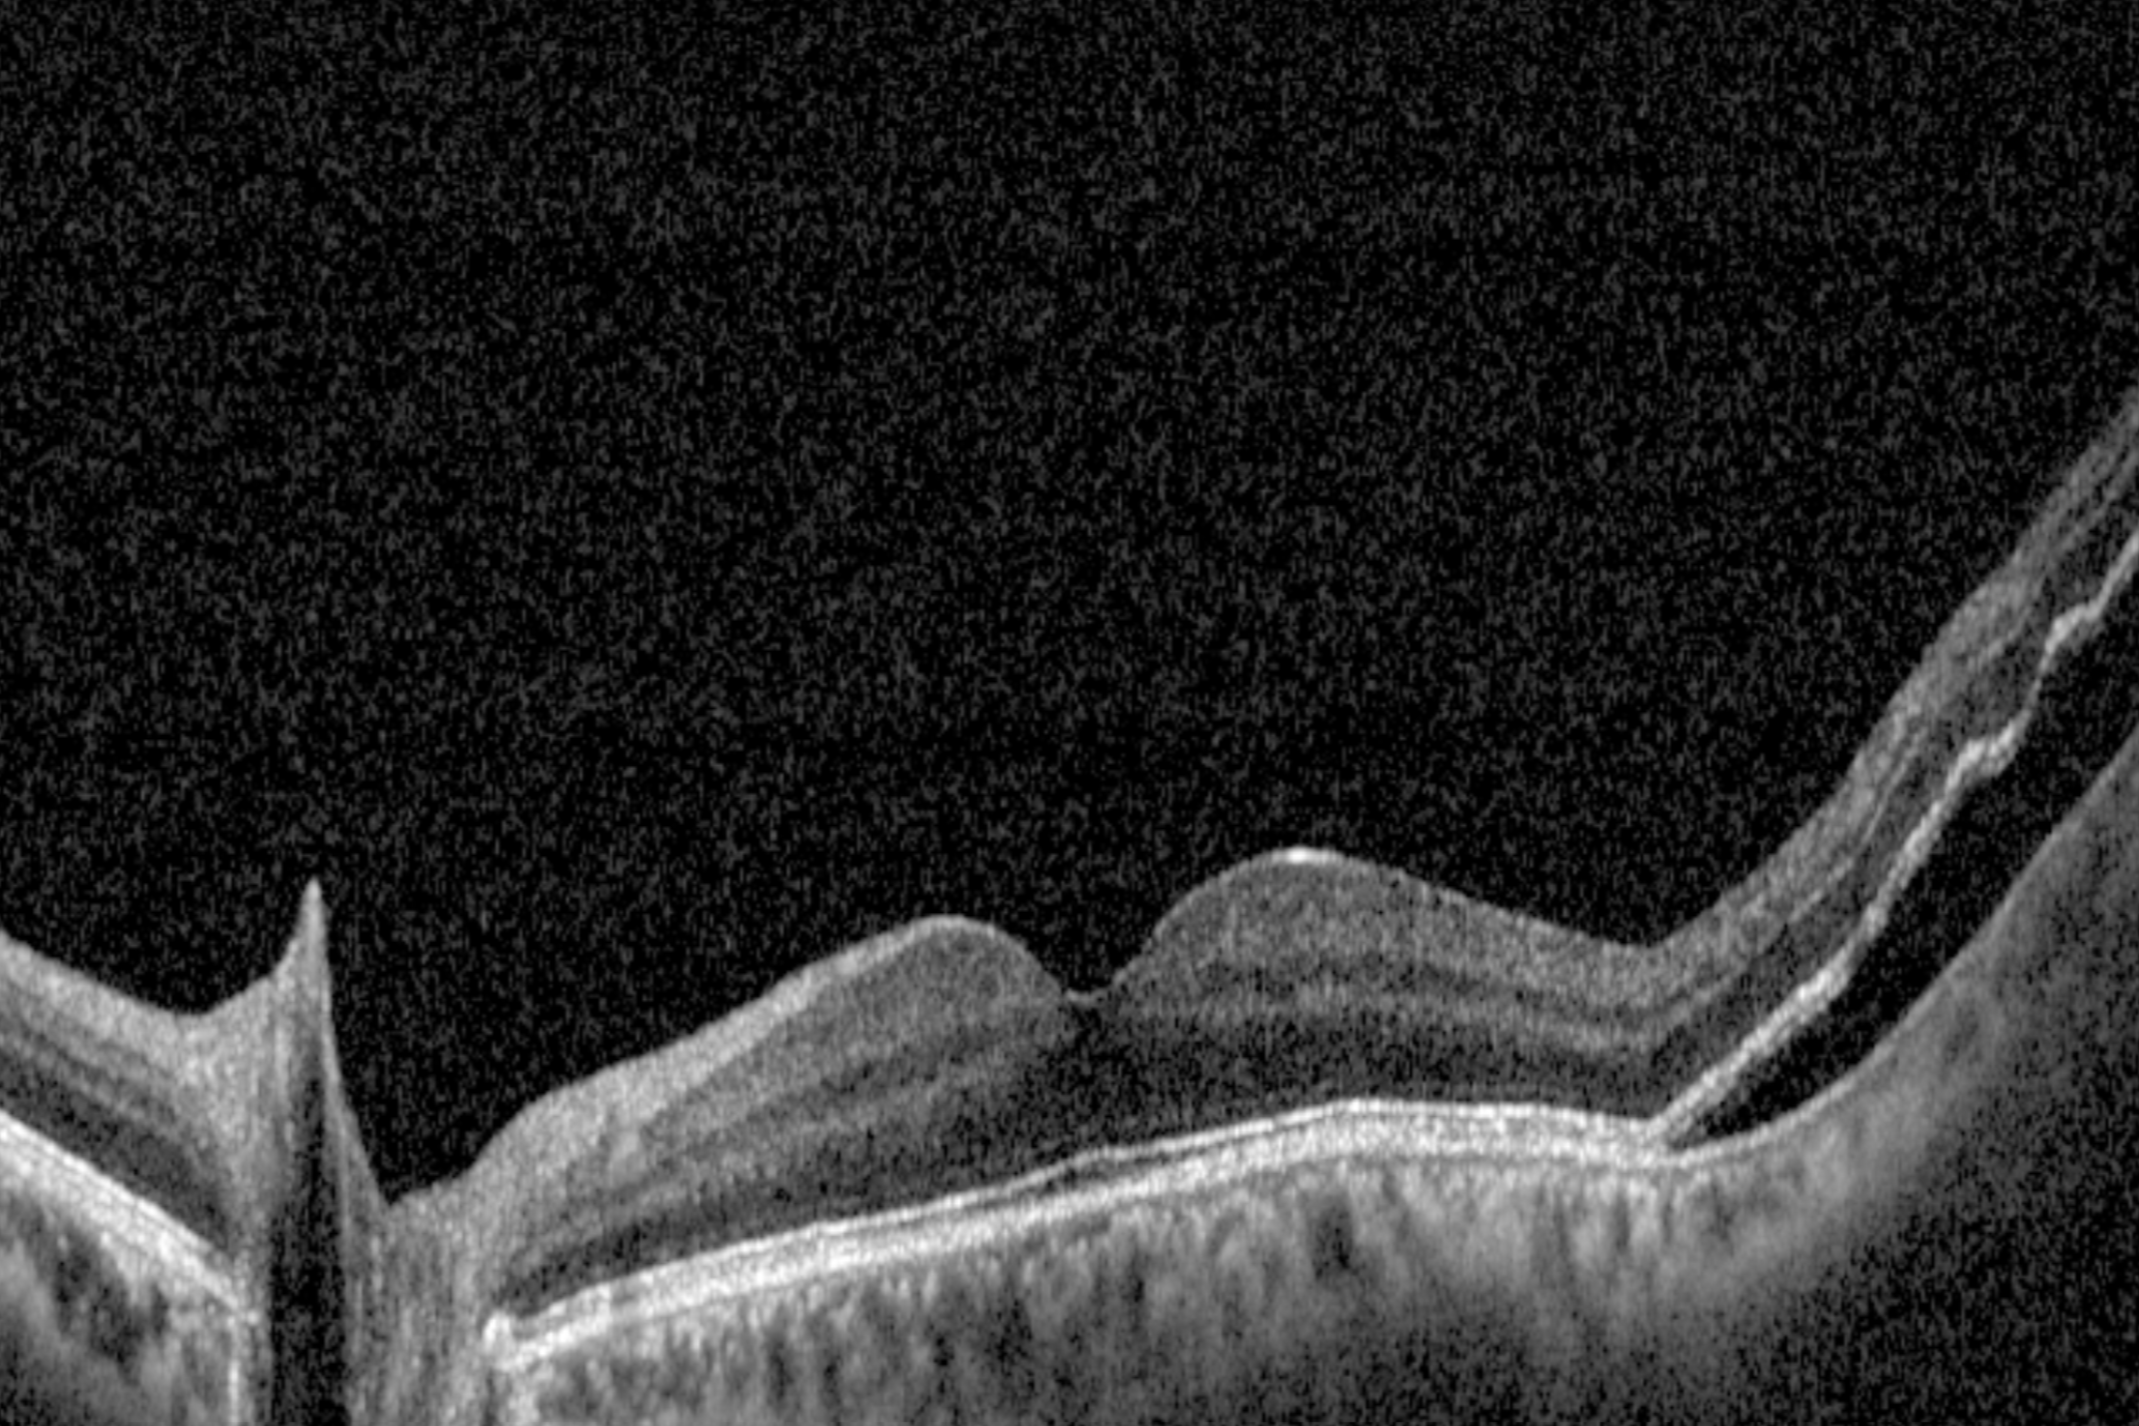

A posterior vitreous detachment is common with age and often harmless. However, because PVD can cause traction, it sometimes leads to retinal tears or detachment. Our optometrists can confirm the diagnosis with a dilated fundus exam.

We use dilated fundus exams, scleral depression, and retinal imaging to carefully examine the retina. This ensures tears or detachments are identified early.